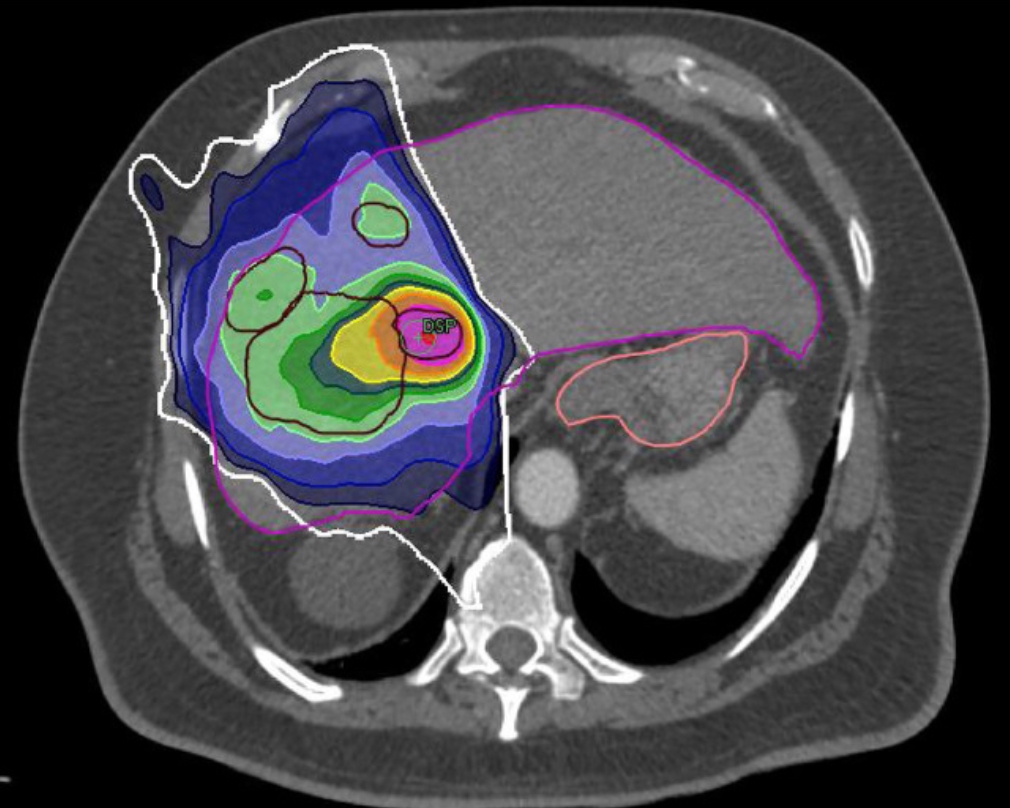

Il s’agit donc de quantifier la précision géométrique et l'impact dosimétrique du contourage des organes à risque de l'abdomen supérieur par les techniciens en radiothérapie à partir d'images IRM. Pour ce travail, huit MEM et cinq radiothérapeutes ont délimité six organes à risque sur les images IRM de trois cas de cancer primitif du foie. Le plan de traitement a ensuite été recalculé et les contours obtenus ont servi à générer des histogrammes dose-volume pour les organes à risque. Le coefficient de similitude de Dice (DSC), la distance de concordance et les doses à des volumes critiques des organes à risque ont été utilisés pour quantifier les différences entre les contours des MEM et ceux des radiothérapeutes.

La comparaison des contours a révélé un DSC ≥ 0,7 pour chaque patient et chaque organe. D’autre part, les doses moyennes étaient inférieures à 5 % pour 10 organes à risque sur 24. Les contours des MEM ont induit des différences moyennes de dose supérieures de 5 % dans 7 organes à risque et inférieures de 5 % dans 7 autres. Des doses plus faibles ont été observées pour le duodénum, le gros et le petit intestin. Les différences de dose entre les contours des MEM et des radiothérapeutes n'étaient pas significativement corrélées au DSC. L'impact dosimétrique de la variabilité de délimitation variait considérablement d'un patient à l'autre.